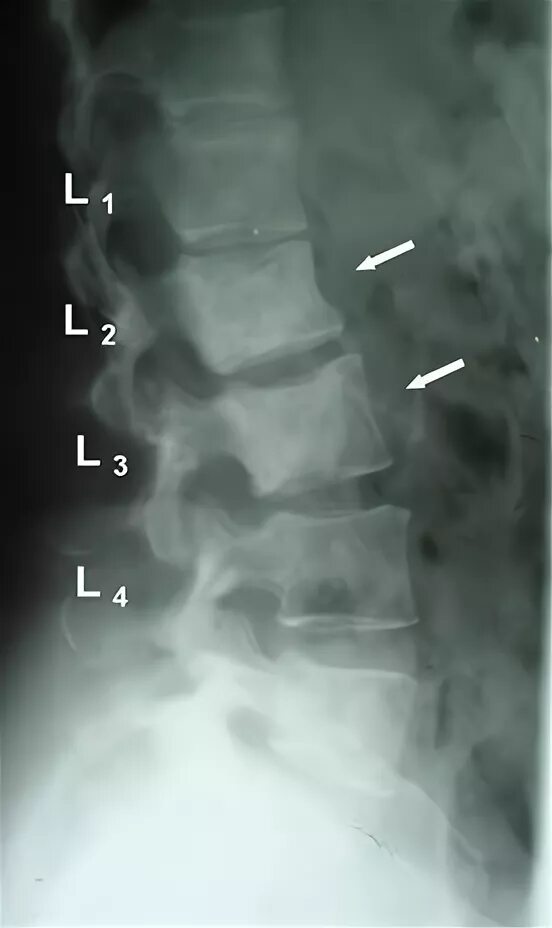

4 стадия метастазы позвоночника